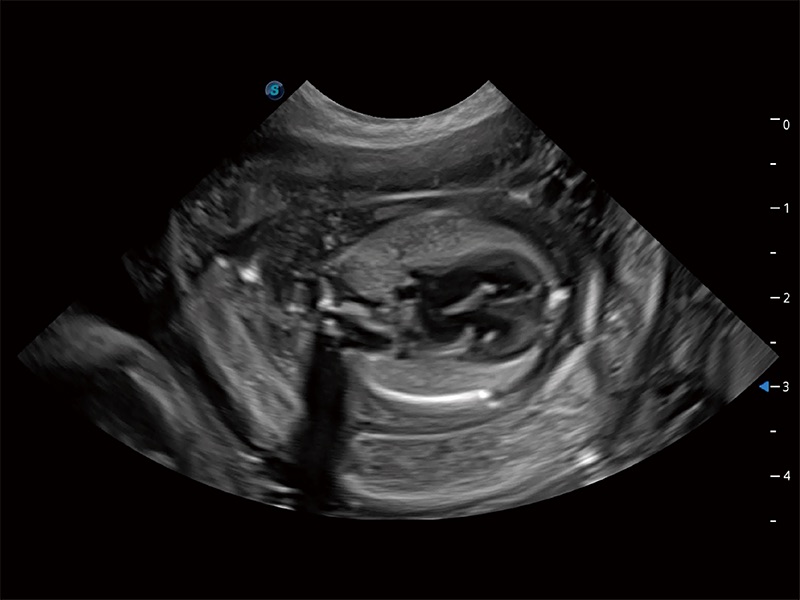

(犬)胎儿主动脉弓立体血流

(犬)胎儿四腔心